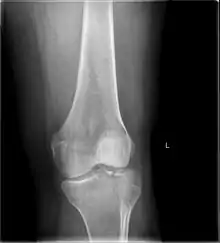

| A severe tibial plateau fracture with an associated fibular head fracture | |

A tibial plateau fracture seen on X-ray